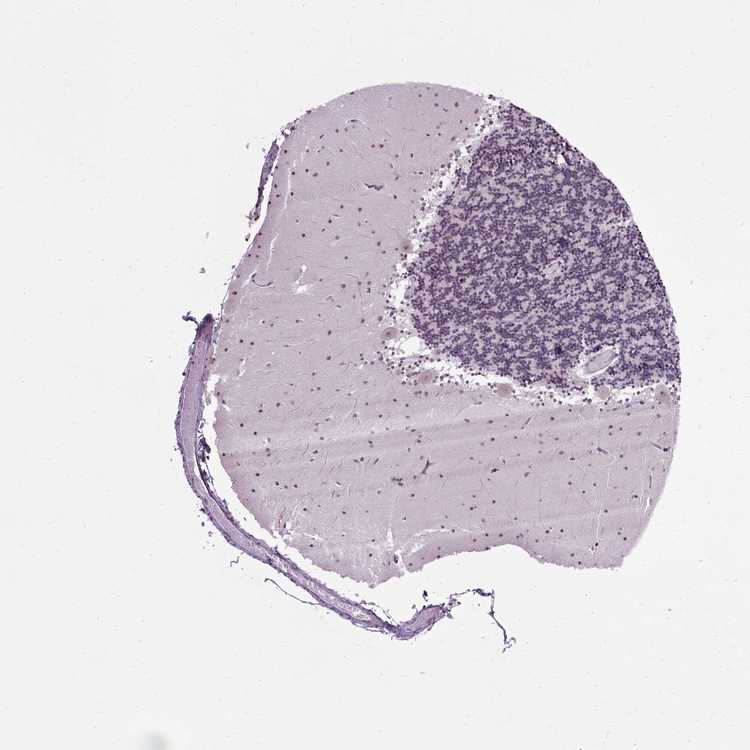

CEREBELLUM - Antibody stainingi

Antibody staining in the annotated cell types in the current human tissue is reported as not detected, low, medium, or high, based on conventional immunohistochemistry profiling in selected tissues. This score is based on the combination of the staining intensity and fraction of stained cells.

Each image is clickable and will lead to virtual microscopy that enables deeper exploration of all samples and also displays staining intensity scores, fraction scores and subcellular localization as well as patient and tissue information for each sample.

Antibody HPA019730

Purkinje cells Medium

Cells in granular layer Low

Cells in molecular layer Medium